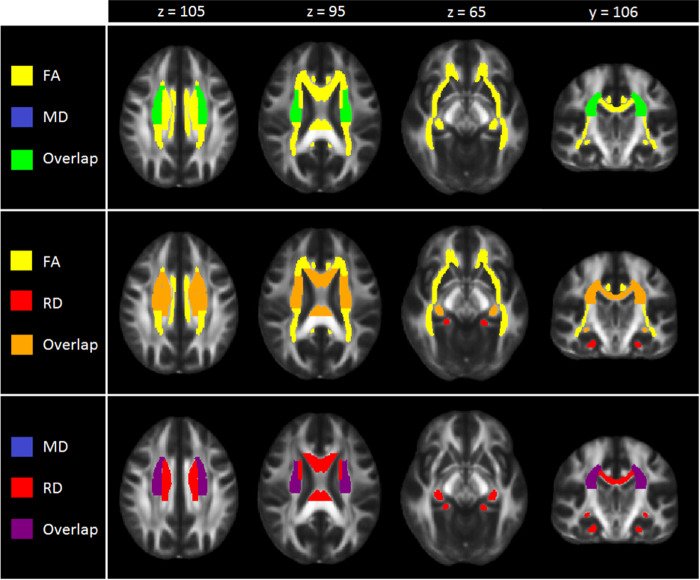

Fig. 2.

Regional overlap in case-control differences in white matter integrity across adults and adolescents

After FDR correction, significantly lower FA was observed for adult MDD patients (N = 921; age range 22–88) compared to healthy controls (N = 1265) in 16 of the 25 ROIs, with the largest effects observed for the full WM skeleton, followed by the anterior corona radiata (ACR), corona radiata (CR), corpus callosum (CC), genu of the corpus callosum (GCC), body of the corpus callosum (BCC) and anterior limb of the internal capsule (ALIC). Significantly lower FA was also observed in the superior fronto-occipital fasciculus (SFO), sagittal stratum (SS), internal capsule (IC), posterior corona radiata (PCR), superior corona radiata (SCR), inferior fronto-occipital fasciculus (IFO), fornix/stria terminalis (FXST), external capsule (EC), and cingulate gyrus of the cingulum bundle (CGC) (Fig. 1, Supplementary Table S4 and Supplementary Fig. 1). No significant effects were observed for AD or MD differences in adults (Tables S4 and S6 and Supplementary Fig. 1). Higher RD for the adult sample was observed across seven ROIs, including the FXST, BCC, SCR, hippocampal part of the cingulum bundle (CGH), the full WM skeleton, CR, and SFO (Fig. 2, Table S7 and Supplementary Fig. 1).

After FDR correction, no significant differences were observed for FA, AD, MD, or RD between adolescent MDD patients (N = 372) and healthy controls (N = 290) (Tables S8–11 and Supplementary Figures. 2 and 3).